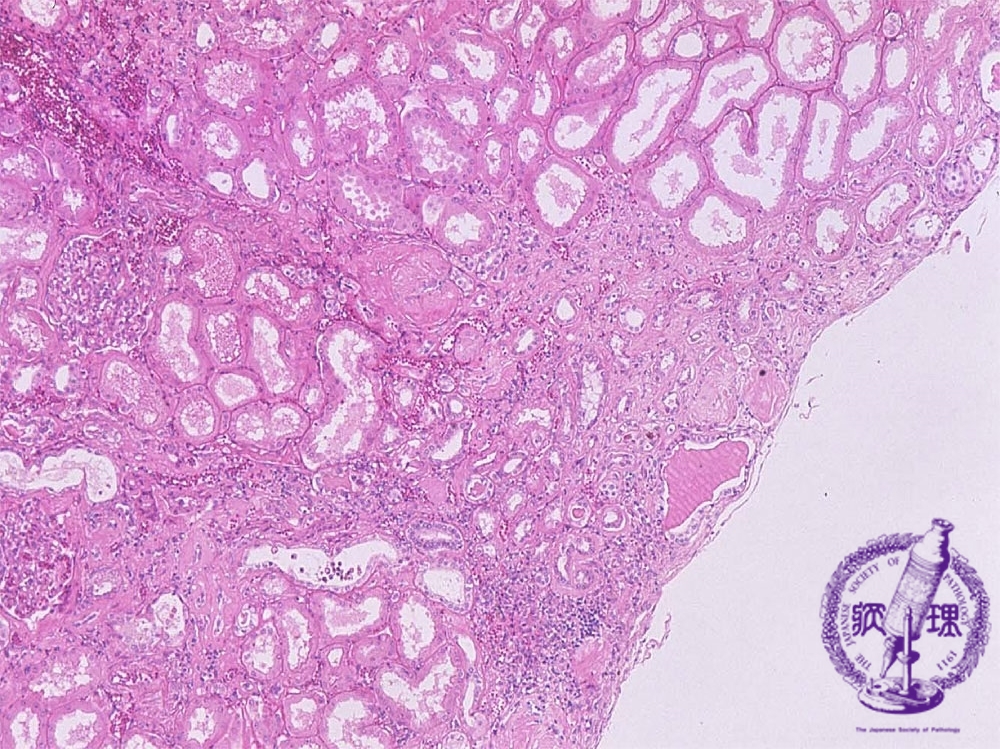

- ★(10)Nephrosclerosis(benign nephrosclerosis)

Microscopic image (HE, mid-power): The cortex shows wedge-shaped atrophy (yellow dotted line) with scar and a mononuclear cell infiltrate.